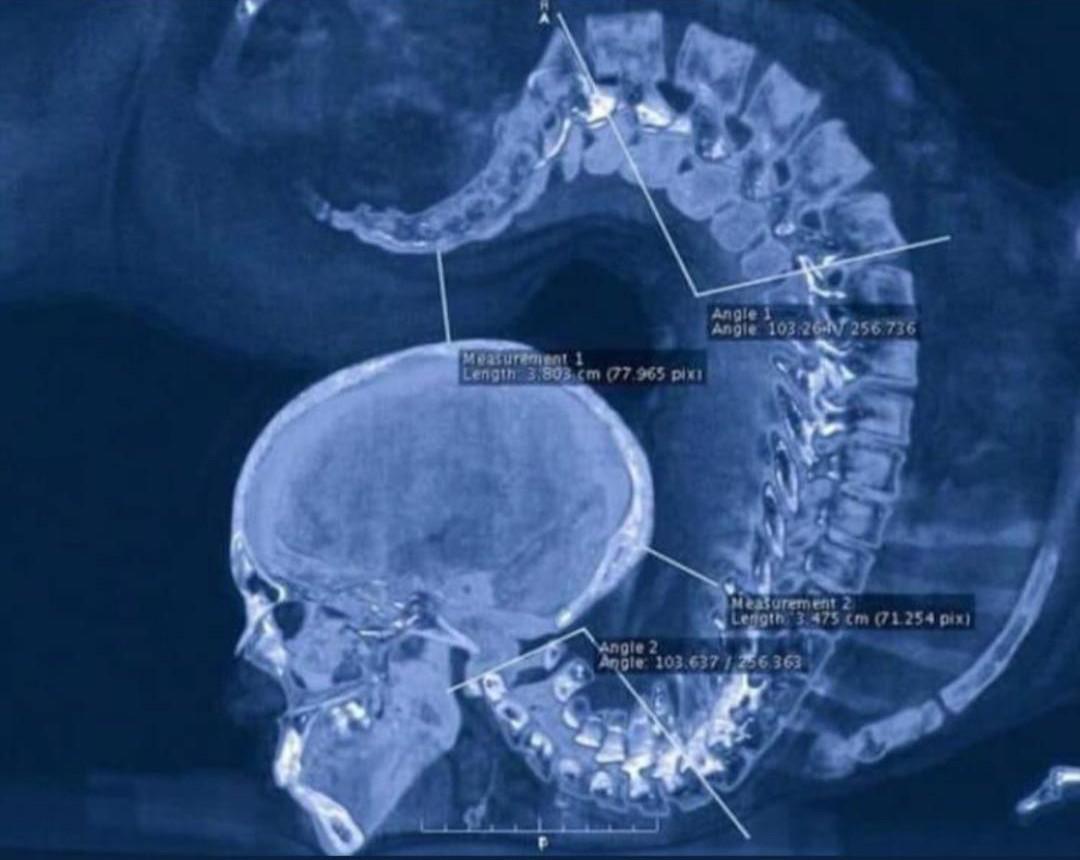

XRay of a gymnast doing a floor exercise looks like a Mortal Combat X Ray Gymnast To diagnose a distal radial epiphysis fracture, a doctor performs a physical exam and determines the overall state and functional capacity of the wrist. Gymnast's wrist is a distal radius physeal injury most commonly due to overuse of the wrist primarily affecting young gymnasts. Gymnast wrist occurs when a gymnast repetitively impacts or pounds on her/his wrists and causes a. X Ray Gymnast.

Xray of a gymnast doing a floor exercise. Thanks to James Mateika for X Ray Gymnast Gymnast wrist occurs when a gymnast repetitively impacts or pounds on her/his wrists and causes a stress fracture or injury/inflammation to occur in. Swelling and reduced range of motion at the wrist. To diagnose a distal radial epiphysis fracture, a doctor performs a physical exam and determines the overall state and functional capacity of the wrist. Diagnosis is made clinically. X Ray Gymnast.